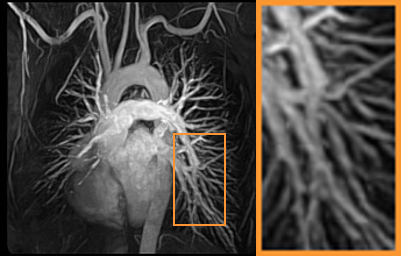

To demonstrate the robustness of our approach, we first apply it on various MRI data including the chest, cardiac and renal (?). In Tab. 2, Our proposed framework gives the highest PSNR for all of the tree types of MR images. Fig. 7 visualizes the corresponding results for chest data. we can see that our approach prevails over others in detail restoration at the junction of blood vessels as well as noise removal in the background. Actually, our method has a stronger ability to handle slight noise because of the subprocess of learning based optimization with deep prior. To demonstrate that, we add Rician noise at level of 20 to 25 T1-weighted MRI and 25 T2-weighted MRI to generate the noisy data. As what is shown in Fig. 8, our method over leads all the competitors by a large margin when the input is corrupted with Rician noise.

Benchmark: We then compare our method with other CS-MRI techniques on the task of CS-MRI with noise. The -weighted and -weighted MRI data in IXI dataset are adopted as test benchmark. Since the compared methods don’t have mechanism to handle Rician noise, we separately assign a classical Rician noise remover RicieOptVST and our learnable architecture for them to execute the denoising after CS reconstruction. As shows in Tab. 3, our CS-MRI framework has superiority against others based on both RicieOptVST and our network. Furthermore, the choice of taking our learnable architecture as the denoiser performs better than that of taking RiceOptVST and the last column shows that the proposed framework surpasses all the combinations. In Fig. 10, we can have a more intuitive understanding to the reconstruction comparison. More details are preserved in our framework than competitive approaches.